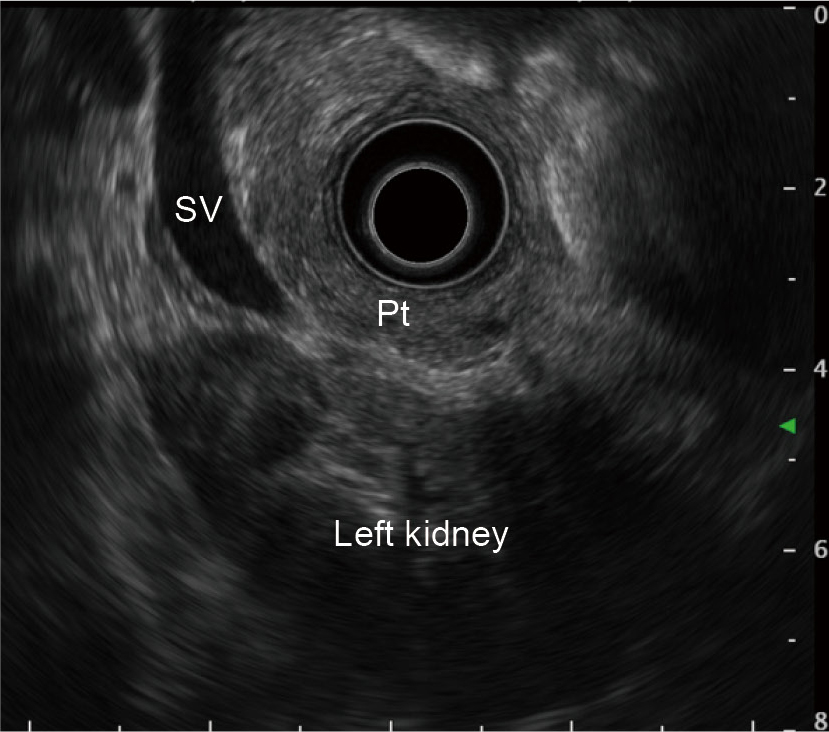

While rotating the scope clockwise and pulling it slightly, follow the pancreatic parenchyma and main pancreatic duct to observe the pancreatic tail. Use the splenic vein and left kidney as landmarks.

The pancreas is sometimes difficult to visualize due to pancreatic atrophy or fatty replacement (fatty infiltration). Should this be the case, pull the scope as close as possible to the esophagogastric junction in transgastric operation so that a cross-sectional image of the aorta appears right below the transducer. Rotate the scope until this is positioned in the six o’clock direction on the screen (Fig. a). While keeping this axis, advance the scope to image the splenic vein; the pancreatic parenchyma is visualized between the splenic vein and the transducer (Fig. b). Alternatively, you can also find the left kidney by scanning the gastric body first and then image the pancreatic tail between the left kidney and the transducer (Fig. c).